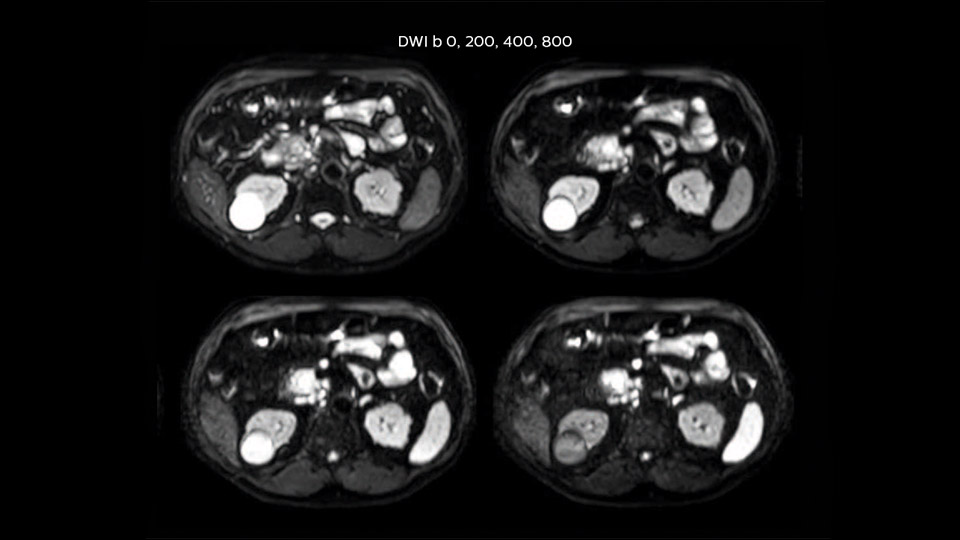

Dr. Baumann then implemented MultiVane XD for motion correction. It uses an extended reconstruction algorithm for imaging that is virtually motion free. “With MultiVane XD we get excellent motion-corrected images with high spatial resolution. We typically first optimize our scan for high image quality, and when satisfied with that, we try to reduce the scan time. So, we combined MultiVane XD with dS SENSE, which allows us to shorten the scan time,” he explains. “The performance of MultiVane XD in liver imaging is outstanding. MultiVane XD with dS SENSE is a powerful development in improving liver image quality.” “As we use breathhold imaging for T2-weighted liver scans, we depend on the patient’s ability to cooperate with the exam. This can present a real challenge when we are looking for small lesions, such as in our oncological patients. However, with MultiVane XD motion correction, we get excellent images. This is important for our surgeons, because they want to know exactly where the lesions are.”

“Our liver exams are quite fast,” says Dr. Baumann. “If the patient tolerates it, we use an arms-up position to reduce the FOV and speed up the exam with dS SENSE.” “We acquire one transversal high resolution T2-weighted sequence with 3 mm slice thickness, for example for pancreas or liver lesions. Then we also add a T2 fat suppressed MultiVane XD SPIR sequence. We perform these two routinely in our liver imaging. We use high dS SENSE factors to significantly shorten scan times to 2-4 minutes, which can improve our protocol; it’s a very robust scan.” “We include mDIXON for the dynamic sequences because of the robust and homogeneous fat suppression we get with that. We had been using eTHRIVE, but we are now quite happy with mDIXON. Sometimes we use a medication to calm the bowels, to further improve the image quality.”

“We are more confident in our diagnosis if we don’t have to rescan the patient and compare it to other studies; this liver exam gives us good image quality in a faster time than the default system’s approach with arms down. That makes a difference for the patients, too. The shorter scan times, especially with the high dS SENSE factors, shorten the duration of the total examination. At the same time it’s more comfortable for the patient, to rest normally without holding the breath, just relaxing.”